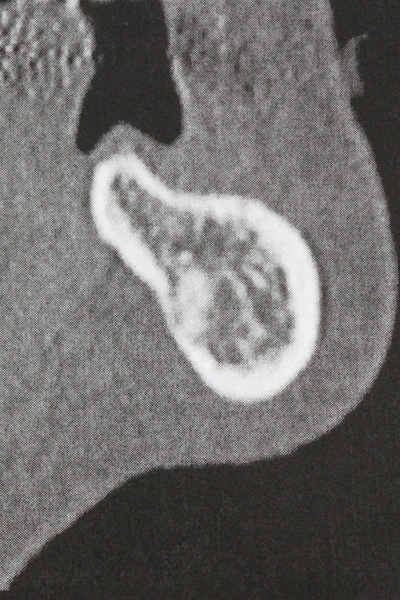

Preparation of the lateral window during an external sinus floor elevation is challenging, particularly for implantologists with little surgical experience. Removal of the bone cover of the sinus without injuring the underlying Schneiderian membrane is only part of the operation – after establishing an adequate access, the membranous lining of the sinus must be carefully mobilized to make space for the augmentation materials or the implants. Piezosurgery is useful for this indication in two ways: diamond-coated instruments can be used for selective bone ablation and the underlying mucous membrane remains intact when the procedure is done carefully. The ultrasonic frequencies also enable detachment of the mucous membrane without complications – the frequencies are transmitted into the space between the mucous membrane and sinus floor by special blunt attachments (Cassetta, Ricci et al. 2012, Pereira, Gealh et al. 2014) (Rickert, Vissink et al. 2013). As a result, it is not surprising that current reviews of external sinus floor elevation positively evaluate the use of piezoelectric devices as well as the use of roughened implant surfaces and bone replacement materials (Wallace, Tarnow et al. 2012).